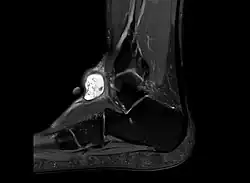

Diagnose

Die Diagnose eines Ganglions kann meist schon durch dessen Lokalisation oder Form gestellt werden. Die darüber liegende Haut ist verschiebbar, es besteht eine unveränderliche Verbindung zum Gelenk oder zur Sehnenscheide. Da aber auch andere Veränderungen ein ähnliches Bild bieten können, ist meist eine Sicherung der Diagnose nötig. Dies kann beispielsweise durch Nadelaspiration der Flüssigkeit, Ultraschall oder chirurgische Intervention geschehen. Im normalen Röntgenbild ist ein Ganglion nicht sichtbar. Die Röntgenaufnahme dient aber zum Ausschluss einer Knochenvorwölbung (Exostose). Besonders an der Basis des dritten Mittelhandknochens kann es auf dem Handrücken zu einer solchen Exostose kommen, die als Carpal boss mit einem Ganglion verwechselt werden kann.